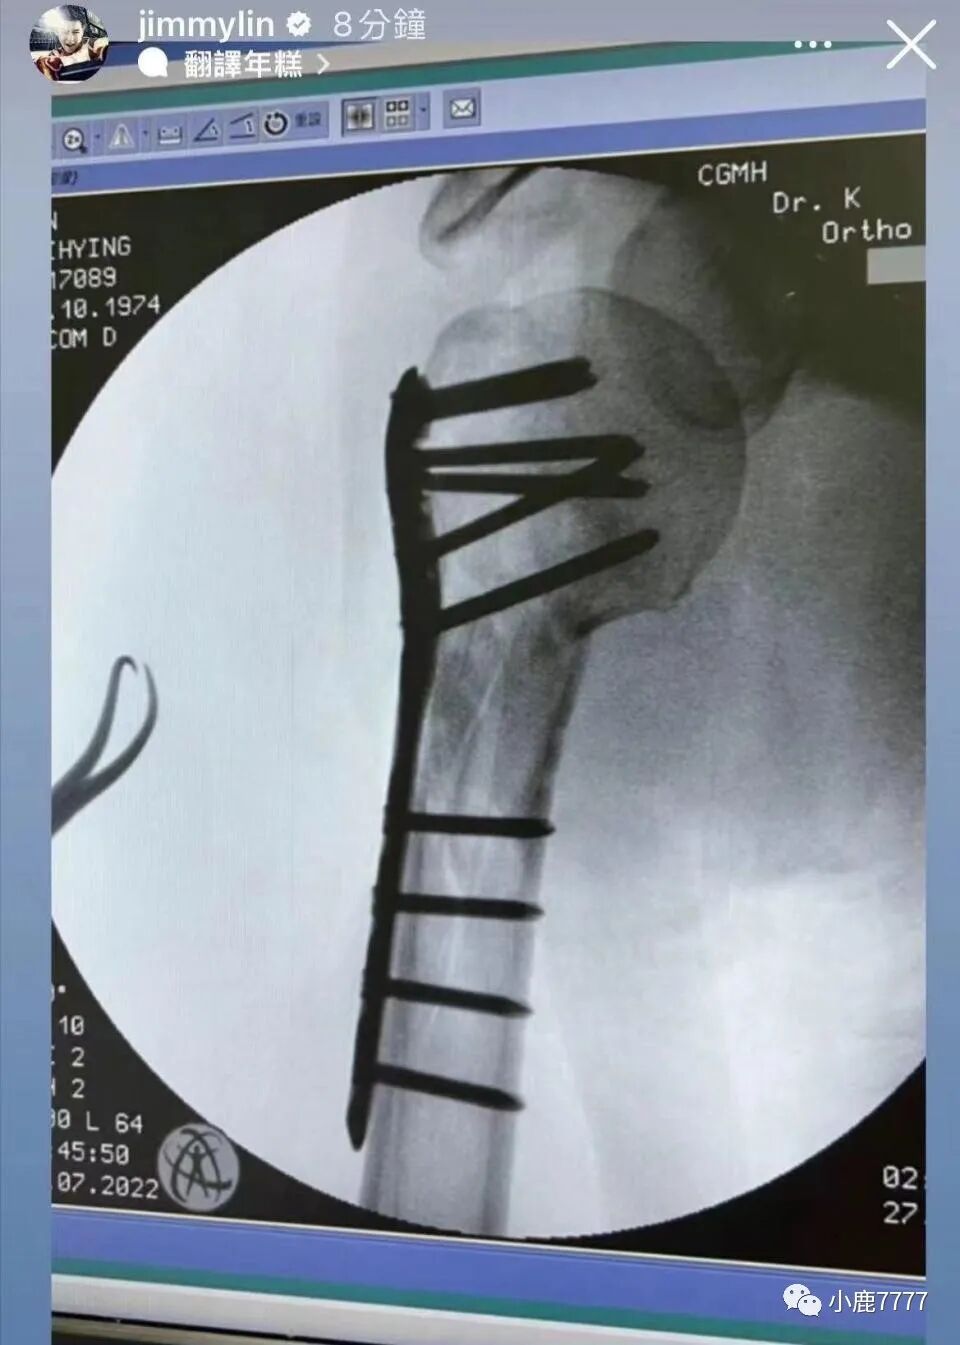

林志颖的康复过程是公开透明的。他从未隐瞒自己的受伤情况,那些镶嵌着钛合金钉子的伤痕不仅令人心疼,也展示了他作为明星对抗命运打击的顽强。